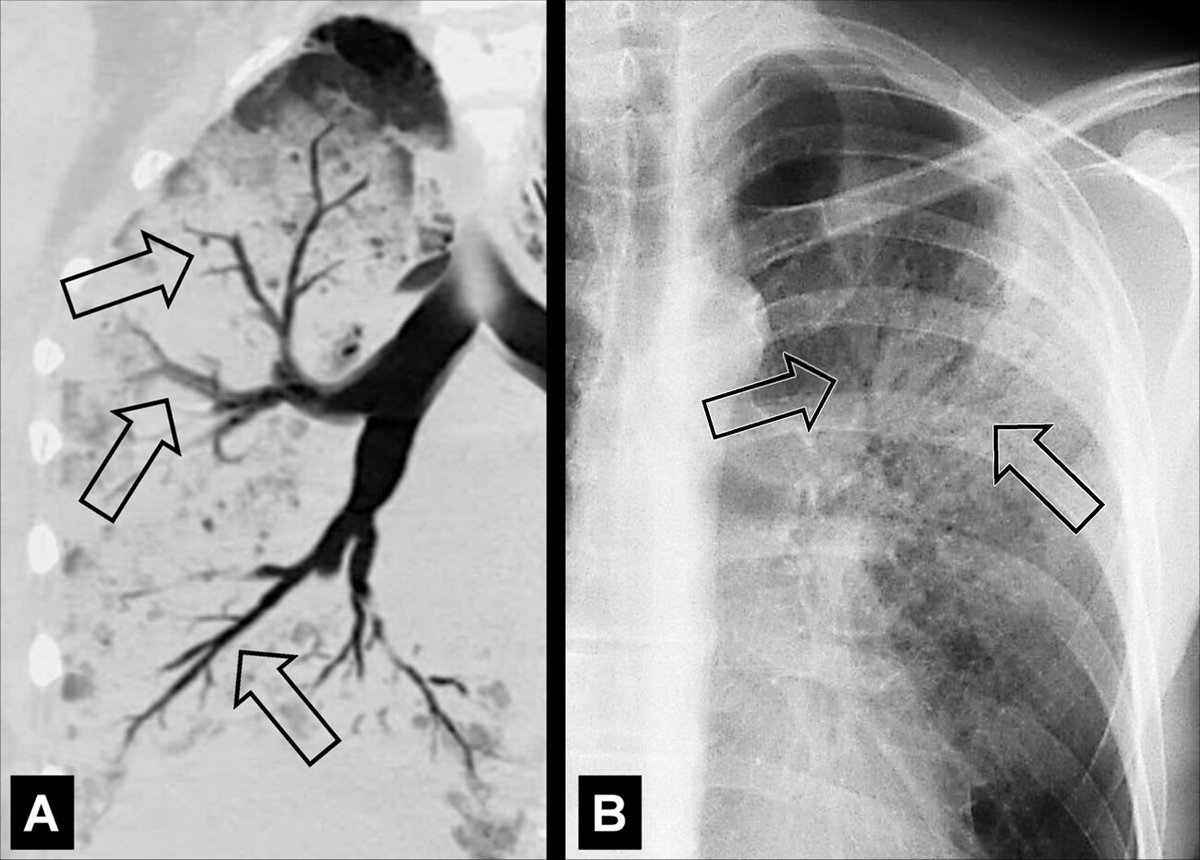

The new edition of the Fleischner Society glossary of terms for thoracic imaging is accompanied by over 150 images, which serve as a visual reference for the terms. https://t.co/dDuBGttmko